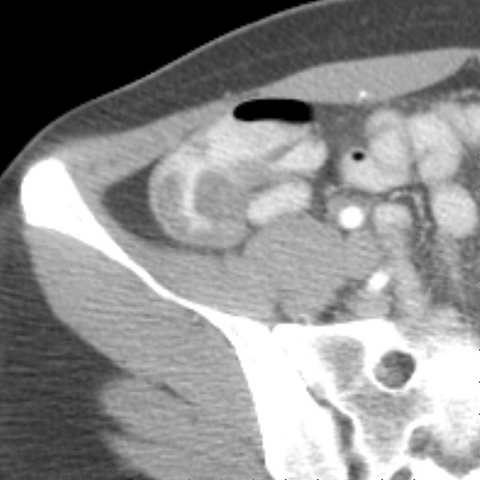

18 year-old male presents with a sudden onset of RLQ pain and rebound tenderness. [1 of 5]